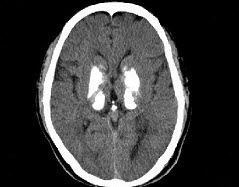

男,49岁,反复发作性癫痫,双手震颤5年,伴头昏行走不稳,生化检查:血清钙降低,血清磷升高,请根据所提供图像,选择最可能的诊断()。

A、Fahr病

B、一氧化碳中毒性脑病

C、霉变甘蔗中毒

D、肝豆状核变性

E、甲旁低

E